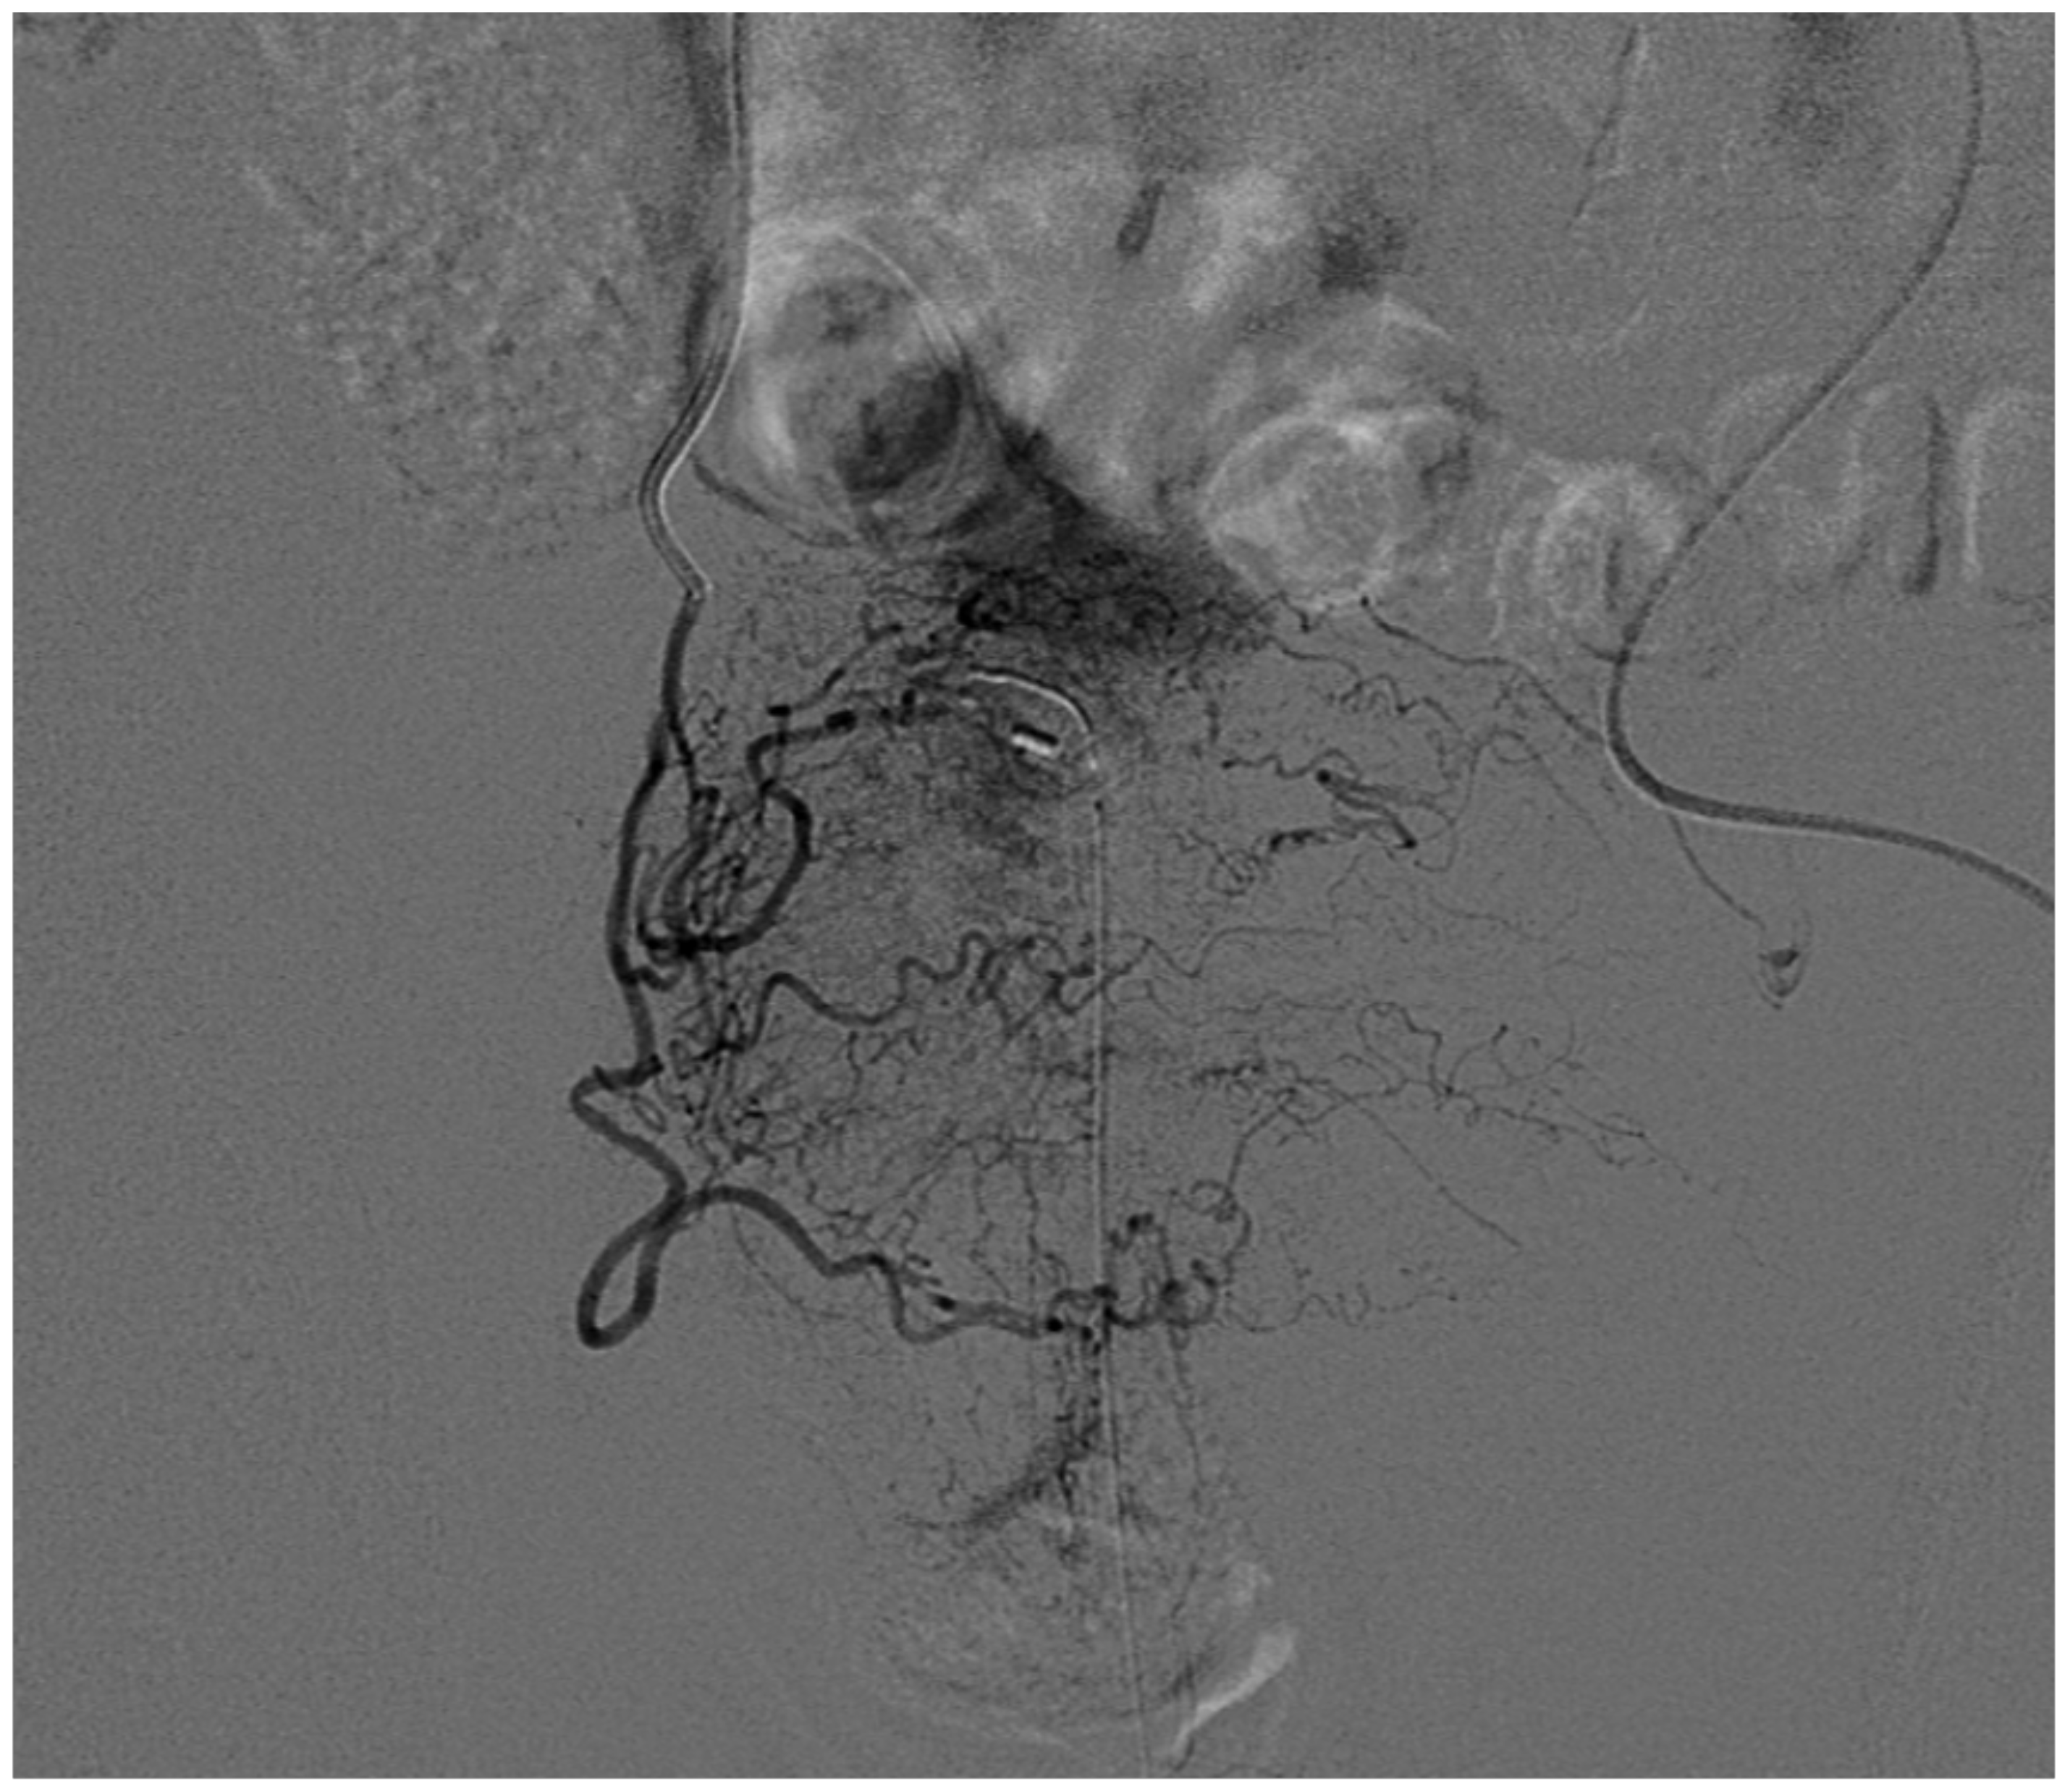

5.1. High-Flow Priapism

5.3. Treatment of High-Flow Priapism